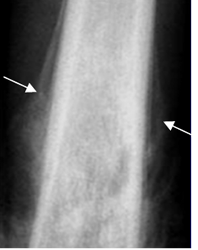

Fig 40. Reacción perióstica agresiva.

Rx AP. Reacción perióstica en capas de cebolla, por la presencia de osteosarcoma.